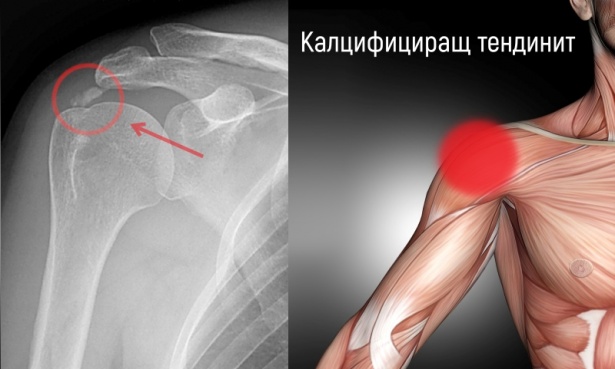

Калцифициращ тендинит представлява заболяване, което се характеризира с отлагане на хидроксиапатит (кристали калциев фосфат) в сухожилието, което причинява болка и възпаление. Най-честата локализация на този процес е ротаторния маншон на рамото и сухожилията около тазобедрената става. Диагнозата се поставя най-често след рентгенография, показваща калциеви отлагания. Обикновено лечението с НСПВС, физиотерапия и инжекции с кортикостероиди дава добри резултати. Тези, при които консервативното лечение не е успешно, се насочват най-често към артроскопска отперация.

Диагнозата калцифициращ тендинит се поставя след снемане на подробна анамнеза и осъществяване на щателен физикален преглед. От образните изследвания рентгенографията, компютърната томография, ехографията и магнитния резонанс, са изключително полезни за точната локализация на процеса и определяне тежестта на уврежданията.